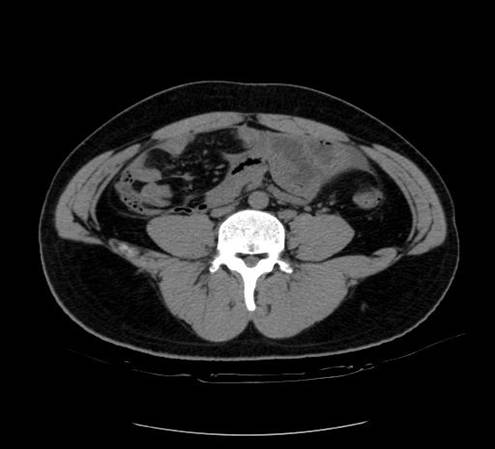

以下是引用zsl6918在2007-6-22 21:08:00的发言:[br]病史较长,反复发作,基本排除恶性病变,腹部定位像可见是小肠梗阻征象,原因无非是肠源性,血管性和神经性的,肠源性的在排除占位后应想到 肠旋转不良的可能,血管性的应想到肠系膜血管的栓塞,神经性的要想到植物神经功能紊乱的可能,本病例应该强化检查帮助诊断,个人感觉旋转不良可能性大。

以下是引用青莲居士在2007-6-24 12:27:00的发言:[br]肠梗阻[br]肝内胆管结石